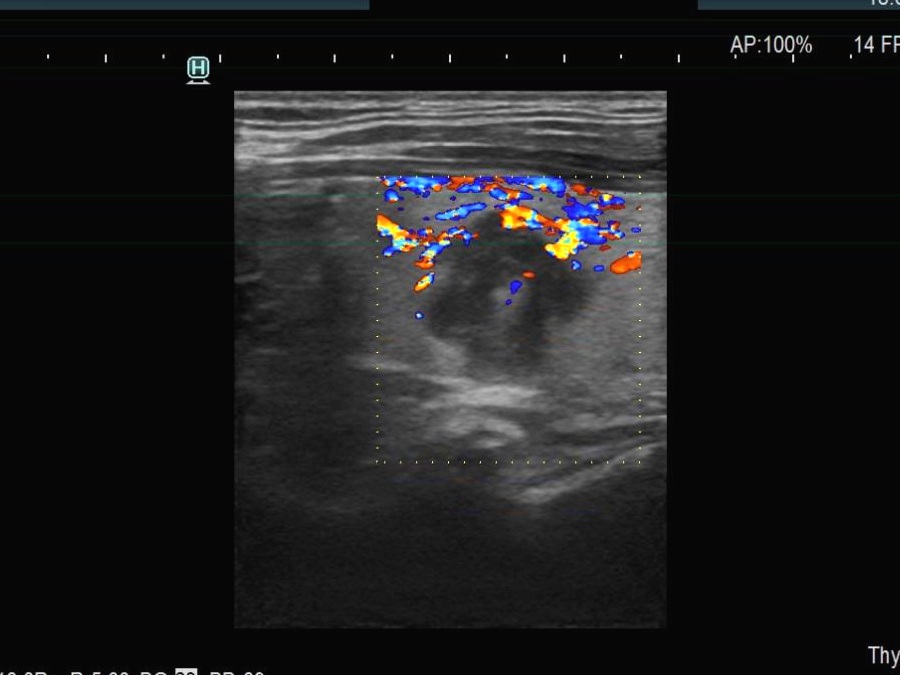

Right lobe, longitudinal scan

Left lobe, longitudinal scan, color Doppler mode. There are some blood flow in the upper part of the nodule.